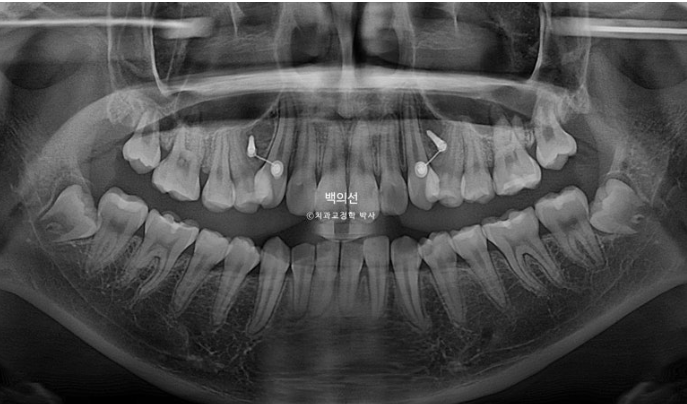

23.05~25.07

파란화살표는 사랑니입니다.

이제 전후 비교 보겠습니다.

인비절라인으로 치료를 시도했던 기간은 1년 3개월(그중에 7개월은 장기 미내원), 클리피씨 장치를 붙여 치료한 기간은 11개월 입니다.

2년 2개월간 치근흡수는 없으며 치근평행도는 좋습니다.

특히 송곳니 덧니 쪽으로 쓰러져 있던 송곳니와 작은어금니 뿌리 치축 개선이 눈에 띕니다.